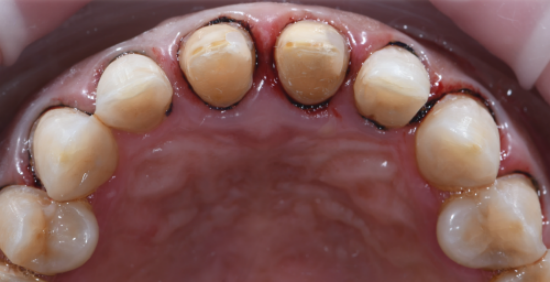

ステップ1: データ収集

セラミックベニアの場合、低侵襲アプローチで最小限の歯構造の縮小を使用することをお勧めします。

デジタルガイド付きベニヤ準備ワークフローは、CADソフトウェアを使用して最終的なベニヤに必要な最小厚さを計算することにより、正確な歯の減少を保証します。